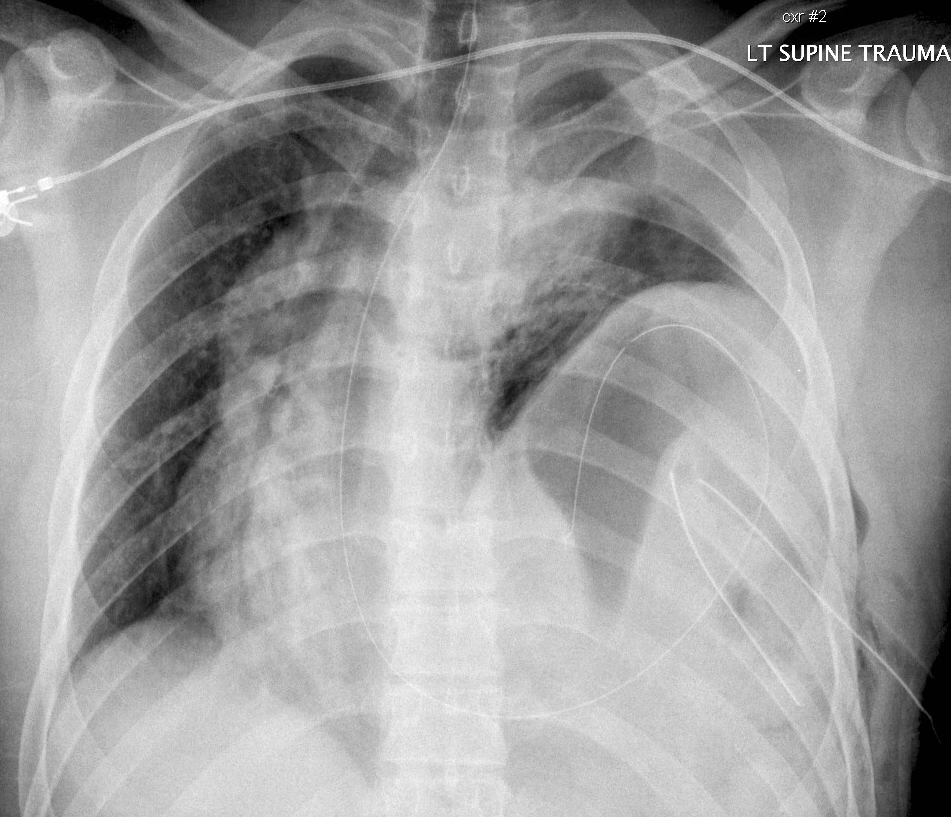

Gallery Blunt Chest Trauma Rupt HD Case 5b

Case 5b